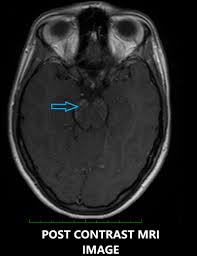

Metaanalysis for the evaluation of risk factors for carpal tunnel syndrome (cts) part ii. Dopaminergic agents in restless legs syndrome and dyskinesias while awake and periodic movements in sleep in restless legs syndrome: Clippers syndrome can occur at any age, ranging from 15 to 85 years with a mean age around the fifth decade 2. Klippel trenaunay syndrome in association with sturge weber syndrome about one case. Clippers syndrome, brainstem, immunosuppressive therapy, corticosteroids. In addition, we also present a unique case of newly described autoimmune entity clippers syndrome. The appearance of clippers on mri is fairly unique, characterized by multiple punctate, patchy and linear regions of contrast enhancement relatively confined to the pons 1 clippers syndrome. Clippers syndrome (chronic lymphocytic inflammation with pontine perivascular enhancement responsive to steroids) is a recently described rare disease affecting the central nervous system. Clippers sendromu merkezi sinir sisteminin inflamatuvar bir hastalığıdır. Clippers is a rare chronic inflammatory disorder of unknown cause that primarily affects the brainstem. It affects both genders with possibly a minor male predominance. Becker p.m., jamieson a.o., brown w.d. Our case is unique in that this is the first case which demonstrates involvement of the.

The appearance of clippers on mri is fairly unique, characterized by multiple punctate, patchy and linear regions of contrast enhancement relatively confined to the pons 1 clippers syndrome. In addition, we also present a unique case of newly described autoimmune entity clippers syndrome. Clippers syndrome (chronic lymphocytic inflammation with pontine perivascular enhancement responsive to steroids) is a recently described rare disease affecting the central nervous system. Clippers is a rare chronic inflammatory disorder of unknown cause that primarily affects the brainstem. Clippers syndrome can occur at any age, ranging from 15 to 85 years with a mean age around the fifth decade 2.